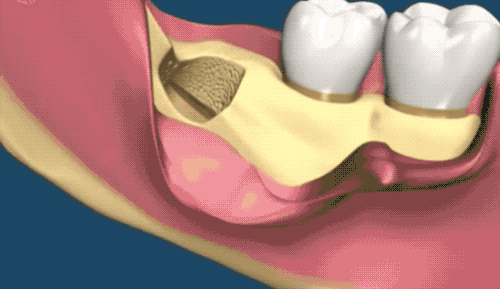

這種款式的橫阻生智齒。一般生長(zhǎng)情況也分兩種,一種是已經(jīng)出肉的,一種是還未出肉的,操作都差不多,我們就直接看下圖的介紹了。

露出牙槽骨后,先削除一部分骨頭,露出躺臥如睡美人的橫阻生智齒...如果是已經(jīng)出肉的智齒,就沒(méi)這一步了。

請(qǐng)出那令人聞聲喪膽的牙科渦輪機(jī),先分割智齒,撬出塊頭過(guò)大的牙冠來(lái)...再把牙根磨切兩半,依次撬出來(lái)。